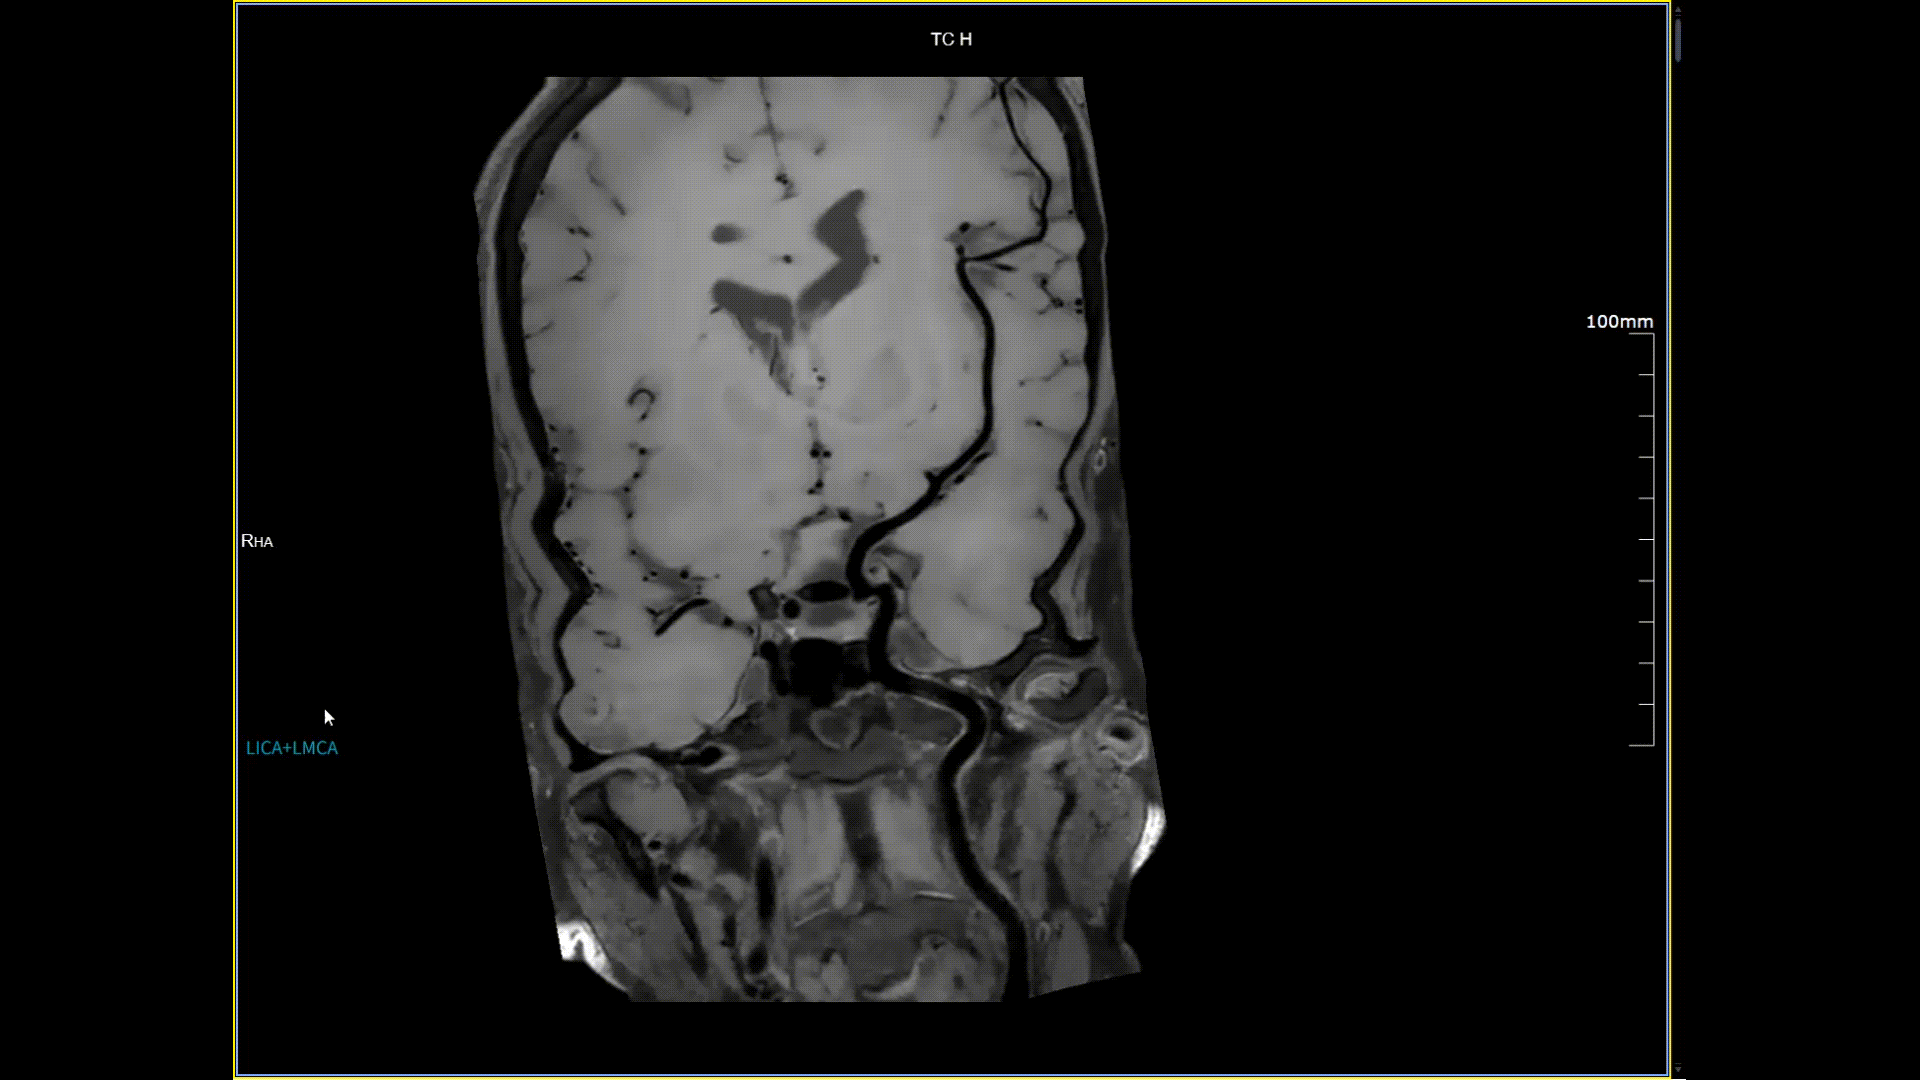

11月3日,一名30歲男性在我院接受了河北省首臺5.0T超高場核磁共振頭顱血管成像檢查,圖像清晰精準地反映出患者右側小腦區域的血管畸形情況,該患者對我院的診療實力與服務溫度給予充分肯定。相較于傳統核磁共振,這臺設備實現了“超高場全身各部位成像”的技術突破,它以業界領先的超高性能實現亞毫米級超高清成像,尤其在神經、心血管、體腹、關節等部位腫瘤疾病的早期發現、精準評估、個性化治療方案制定中提供了的強大影像支持,將為全省乃至周邊地區患者帶來更優質、更精準的醫療服務。

5.0T磁場強度遠高于其他設備,使得氫原子核在磁場中的響應信號極大地增強。這就像在安靜的房間里能聽清細微的聲音一樣,高信噪比能讓醫生看到更微小、更模糊的病變結構。例如上述患者的檢查,該設備可以呈現0.2x0.2毫米高分辨率的圖像以及動態顯示血管走行,使得病變血管的細微解剖結構、分布及其與周邊腦組織的關系得以直觀呈現,為臨床醫生進行精準診斷并制定后續治療方案提供了重要的影像學依據。

頭頸血管斑塊,分辨率0.4*0.4mm